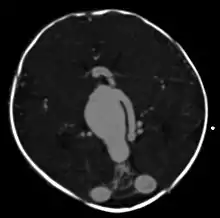

| Large arteriovenous malformation of the parietal lobe | |